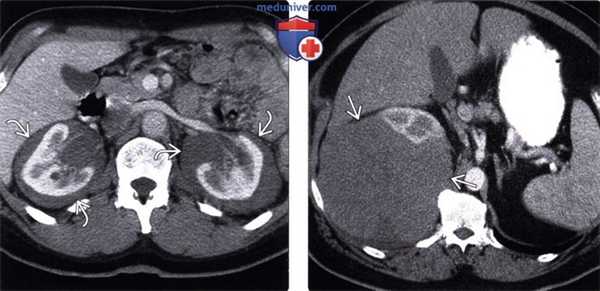

(Слева) При аксиальной КТ с контрастным усилением у пациента после пересадки печени определяется вновь возникшее гиподенсное объемное образование в воротах печени, а также увеличенный портакавальный лимфоузел.

(Справа) При аксиальной КТ с контрастным усилением у этого же пациента определяется выраженная забрюшинная лимфаденопатия. Изменения при посттранспантационном лимфопролиферативном заболевании (ПТЛЗ) в этом случае неотличимы от таковых при типичной неходжкинской лимфоме (НХЛ) у иммунокомпетентного пациента. (Слева) При асиальной нативной КТ визуализируется опухолевидное утолщение стенки сегмента толстой кишки с аневризматическим расширением.

(Справа) Вид в корональной плоскости при КТ с контрастным усилением у этого же пациента: определяется значительное утолщение стенки сегмента кишечника с его дилятацией. Данные изменения характерны как для НХЛ у пациентов с нормальным иммунным ответом, так и для ПТЛЗ.